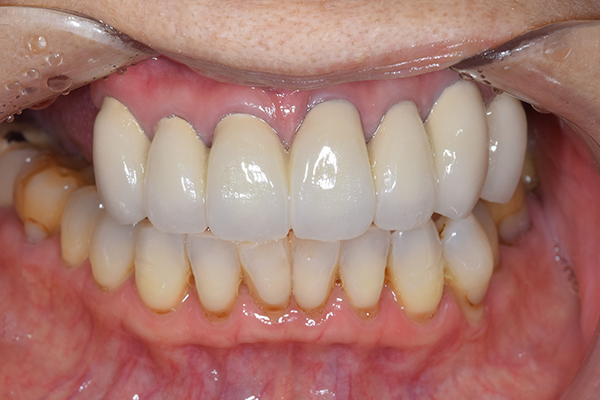

ケース4

(アタッチメントを用いた部分入れ歯)

右上のインプラント周囲炎で、その部分が痛いという患者様でした。 また奥歯で噛むことが難しかったため、前歯を使用することが多くなり、 前歯が前よりも前に出てきていることも気になっていらっしゃいました。

インプラント部以外にも歯周病が進行していましたので、歯周病の治療を行いました。 残念ながらインプラントと、1本の歯が残せなかったため抜歯を行いました。 その後、前歯の出っ張りを修正することと入れ歯の安定を図るため、残っている歯を全てかぶせ物にしていくことになりました。 写真中央は抜歯後に入れた治療用の入れ歯になります。 抜歯後歯ぐきが安定しましたら、入れ歯とかぶせ物の型取りを行いました。

噛み合わせチェックでしっかり奥歯で噛めるようにし、 歯を並べます。 その後、それに合わせて前歯を作っていきます。

最終的な入れ歯用の型取りをします。 シリコンで精密に型取りができました。

こちらが完成したかぶせ物と入れ歯です。かぶせ物にはアタッチメントをつけて金属のバネが見えない構造になっています。 入れ歯自体も金属を使用して、極力違和感がでないように、薄く作成しました。

お口の中に入れた状態です。 非常に見た目もよい出来となりました。 バネがみえないと見栄えが全然ちがいます。

年齢 70代・女性

主訴 奥歯のインプラントが痛い。

前歯がでてきた。

治療期間 6ヶ月

治療費 .メタルボンドクラウン7本:770,000円

.アタッチメント2個:220,000円

.義歯:550,000円

治療方針 ゆれてきたインプラントを抜去した後、歯周病の治療と、予後不良の歯を抜歯して、義歯を作成します。

抜歯後は治療用の入れ歯を作成し、ものが噛める様にします。

また前歯は、被せものをすることにしました。

治療内容 右上のボーンアンカードブリッジ(インプラントのブリッジ)部分がインプラント周囲炎になり、ぐらぐら揺れてきました。

そのため、インプラントを抜去した後、歯周病の治療と、予後不良の歯を抜歯して、義歯を作成していきました。

見た目が入れ歯とわからない様に針金のない、アタッチメントを使用した入れ歯を作成することにしました。

抜歯後は奥歯でものが噛める様に治療用の入れ歯を作成しました。

また前歯はフレアアウト(奥歯で噛めなくて前歯で噛む様になって、前歯が前に出てくる現象)していたため、患者さんの希望でかぶせ物をすることにしました。

特記事項 歯やインプラントを抜いた後は、2〜3ヶ月歯ぐきの回復を待ってから入れ歯を作るため、待機期間があります。その間、治療用の入れ歯を調整しながら使います。かぶせものをした後は歯がしみたり、場合によっては神経を抜く処置が必要になることもあります。